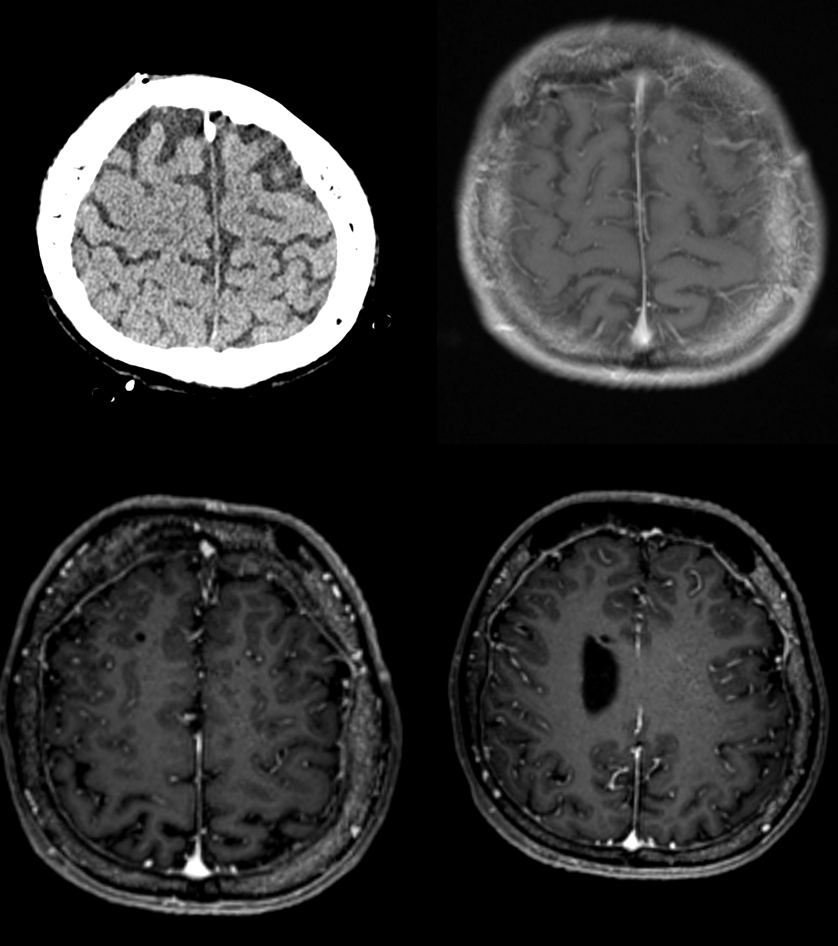

History is complex and unique. There is a convexity dural fistula

Supply is from right primarily. Note something unusual about the MMA — hard to see here